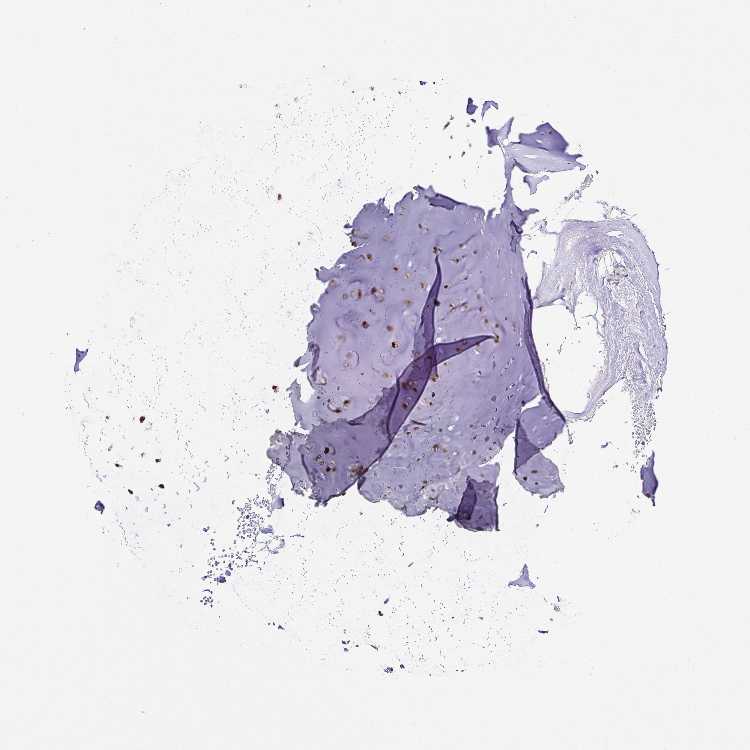

SOFT TISSUE 1 - Antibody stainingi

Antibody staining in the annotated cell types in the current human tissue is reported as not detected, low, medium, or high, based on conventional immunohistochemistry profiling in selected tissues. This score is based on the combination of the staining intensity and fraction of stained cells.

Each image is clickable and will lead to virtual microscopy that enables deeper exploration of all samples and also displays staining intensity scores, fraction scores and subcellular localization as well as patient and tissue information for each sample.

Antibody HPA063330Antibody HPA066216

Chondrocytes Medium-

Fibroblasts Not detectedMedium

SOFT TISSUE 2 - Antibody stainingi

Fibroblasts LowMedium

Peripheral nerve LowNot detected